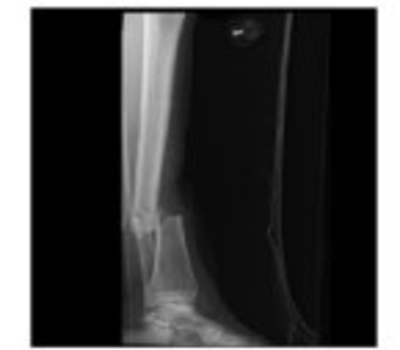

| Open fracture of the shaft of the tibia. | |

Patients with tibial shaft fractures present with pain and localized swelling.[2] Due to the pain they are unable to bear weight. There may be deformity, angulation, or malroation of the leg.[2] Fractures that are open (bone exposed or breaking the skin) are common.[citation needed]

Since approximately one third of the tibia lies directly beneath the skin, open fractures are common compared to other long bones.[1] These open fractures are most commonly caused by high velocity trauma (e.g. motor vehicle collisions), while closed fractures most commonly occur from sports injuries or falls.[3][4] Osteoporosis can be a contributing factor.[3] Skiing and football (soccer) injuries are also common culprits.[4]

Anteroposterior (AP) and lateral radiographs the include the entire length of the lower leg (knee to ankle) are highly sensitive and specific for tibial shaft fractures.[4]